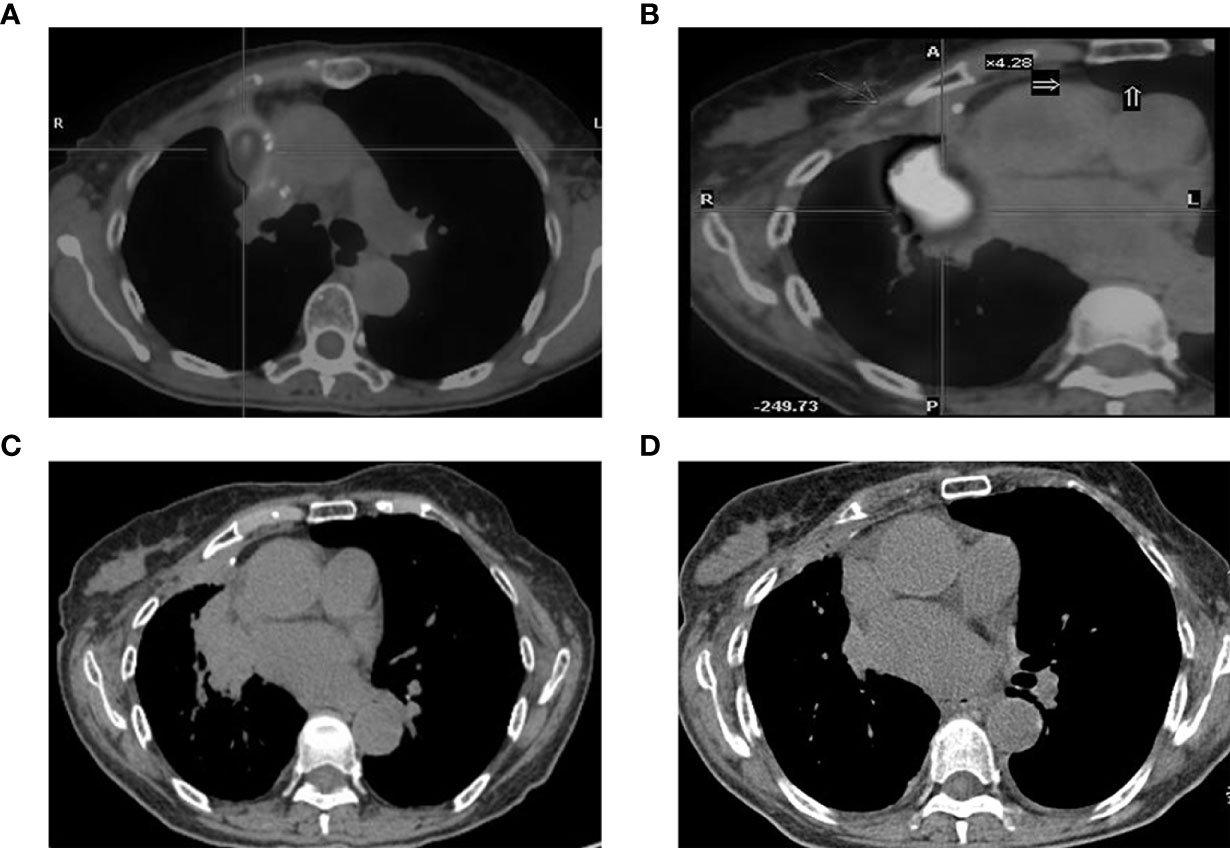

Case Representation

There was one patient whose EGFR mutation status was identified only through BWF samples (Case 6 in Table 2). According to the record, the patient had adenocarcinoma, which was treated surgically in 2008. Four years later, the tumor relapsed as a right hilar mass and was identified as EGFR wild-type through histological samples; the patient then received radiotherapy and chemotherapy (Figure 4). In May 2017, the tumor progressed with an increased right pulmonary mass (Figure 4). Bronchoscopic biopsy failed to obtain adequate tumor tissue to establish the diagnosis, and EGFR mutation detection using forceps biopsy and plasma samples showed EGFR wild-type. However, in both supernatant and sediment BWF samples, EGFR mutations in exon 21 (L861Q) were detected. The patient received afatinib for two months and showed an improvement in clinical status. A chest CT revealed good partial response (Figures 4C). The patient has remained stable to date, i.e., 30 months after the initial diagnosis. This case suggests that BWF could be a reliable basis to determine EGFR mutation status in biopsy-negative cases, avoiding further invasive biopsy procedures.

Figure 4 CT findings. (A) tumor status at diagnosis; (B) the increased tumor progress; (C) chest CT scan result before the afatinib treatments and (D) the chest CT scan result after two months of afatinib treatments. CT, computed tomography.